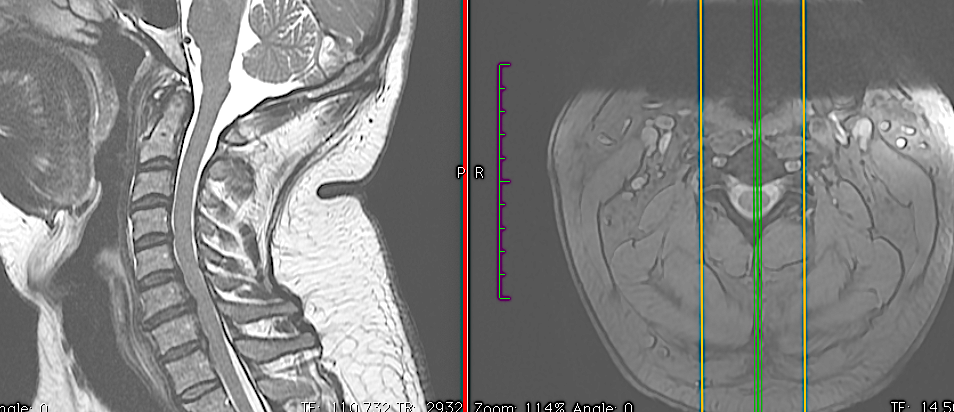

CASO CLÍNICO 2: HERNIA DISCAL C7-TH1 ASOCIADA A ESTENOSIS DE CANAL

Paciente de 46 años que consulta por clínica de mielopatía cervical de evolución progresiva en los últimos dos meses. Tuvo una braquialgia derecha 4 meses antes que mejoró con tratamiento conservador.

Este caso me parece interesante porque hubiese podido ser tratado por vía posterior al ser una hernia lateral, sin embargo, no se trataba de una afectación segmentaria aislada sino que en la misma RM podía apreciarse estenosis de canal en C6-C7 con compresión medular a dicho nivel. No hay que olvidar que el motivo de la consulta fue la instauración de una mielopatía cervical progresiva (inestabilidad, urgencia miccional e hiperreflexia) pues la braquialgia derecha estaba en proceso de remisión.

Por las razones expuestas, a pesar de un thoracic inlet angle bastante alto, opté por realizar un abordaje anterior con descompresión + artrodesis IS con cajas atornilladas C7-Th1.